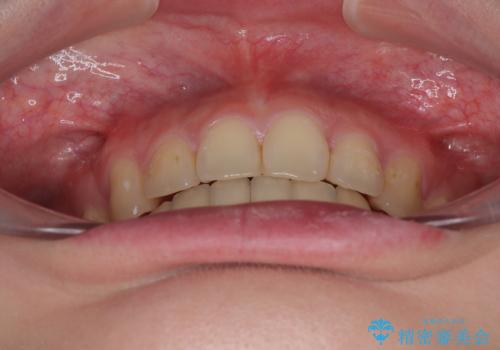

深い咬み合わせは上顎前歯を引っ込ませる大きな障害となるため、咬み合わせの改善が非常に重要となります。やや期間はかかりましたが、当初狙った通りの仕上がりで治療を終えることができました。